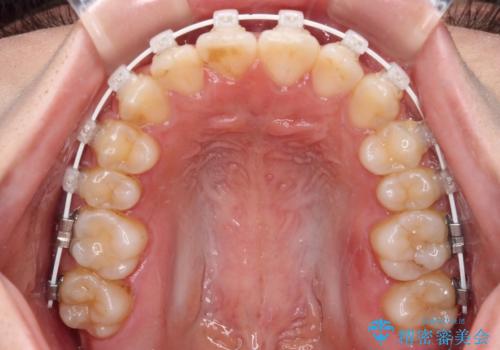

当初予定通り、1年で治療を終えることができました。

後戻り防止はマウスピースで行うため、急に自己管理が必要となるため、移動の最後をマウスピース矯正で行うことで、マウスピース非装着による後戻りリスクを回避する工夫をしています。